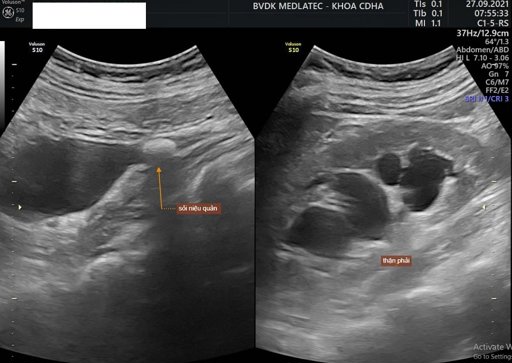

Tổng quan về bệnh sỏi niệu quản

Sỏi niệu quản là một trong những căn bệnh thường gặp và có thể để lại nhiều biến chứng nguy hiểm nếu không được điều trị sớm. Việc tìm hiểu những thông tin cơ bản về tình trạng sỏi xuất hiện ở niệu quản sẽ giúp bạn sớm phát hiện cũng như có biện pháp phòng tránh phù hợp cho chính mình.

Cảnh giác với biến chứng sỏi niệu quản

Sỏi thận rơi xuống niệu quản là một trong những nguyên nhân phổ biến gây ra sỏi niệu quản. Nếu không được khắc phục sớm, có thể dẫn tới tình trạng bít tắc dòng tiểu và gây ảnh hưởng nghiêm trọng đến sức khỏe người bệnh. Những thông tin dưới đây sẽ giúp bạn hiểu rõ hơn về các biến chứng sỏi niệu q...